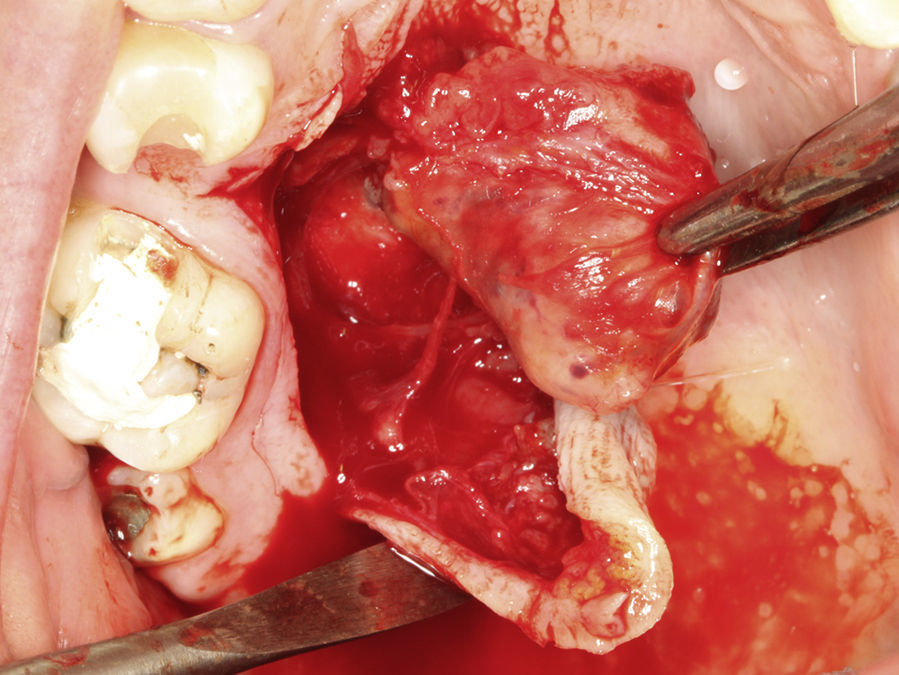

Paciente do sexo feminino, 31 anos de idade, leucoderma, foi encaminhada pelo cirurgião‐dentista à Clínica de Estomatologia do Departamento de Odontologia da PUC Minas para avaliação de lesão nodular no palato duro com diagnóstico histopatológico de adenoma pleomórfico, obtido por meio de biópsia incisional. Durante a anamnese, a paciente relatou a evolução da lesão há 4 anos com característica assintomática. Relatou estar no sexto mês de gestação e não apresentava outras alterações sistémicas. O exame extraoral mostrou ausência de alterações. Ao exame intraoral, observou‐se um aumento de volume bem delimitado no palato duro do lado direito, de consistência firme e coloração semelhante à da mucosa normal, medindo aproximadamente 2,5cm, exibindo pequena área de ulceração no local da realização da biópsia incisional (fig. 9). O exame radiográfico não mostrou alterações. O tratamento proposto foi a remoção cirúrgica conservadora e confecção de placa palatina em acrílico com grampos retentores para minimizar o desconforto pós‐operatório. Foi realizada anestesia local com lidocaína 2% e epinefrina 1:100.000 (ALPHACAINE 100®, DFL, Rio de Janeiro, Brasil), seguida de incisão semilunar com bisturi lâmina 15 (Solidor, São Paulo, Brasil) e rebatimento do retalho mucoso. Como a lesão se apresentava encapsulada, foi possível destacá‐la da mucosa suprajacente com facilidade (fig. 10). O retalho foi reposicionado por meio de pontos isolados (fig. 11) e a lesão (fig. 12) foi fixada em formaldeído a 10% para realização de exame anatomopatológico no Laboratório de Patologia Bucal da PUC Minas. Em seguida, foi colocada a placa de acrílico (fig. 13) para proteção da região operada e controlo da sintomatologia dolorosa.

Os cortes histológicos mostraram neoplasia benigna de glândula salivar, envolvida por cápsula de tecido conjuntivo fibroso (fig. 14). O parênquima neoplásico é constituído por células epiteliais dispostas em lençóis e estruturas ductiformes, além de células mioepiteliais formando áreas mixoides e hialinas (fig. 15) ou apresentando‐se com morfologia plasmocitoide (fig. 16). O diagnóstico de adenoma pleomórfico foi confirmado. A paciente relatou ausência de dor no pós‐operatório e manteve utilização da placa de acrílico por 4 semanas. A paciente encontra‐se em acompanhamento e o exame clínico após 2 anos da remoção cirúrgica mostrou adequada cicatrização e ausência de sinais de recidiva da lesão (fig. 17).